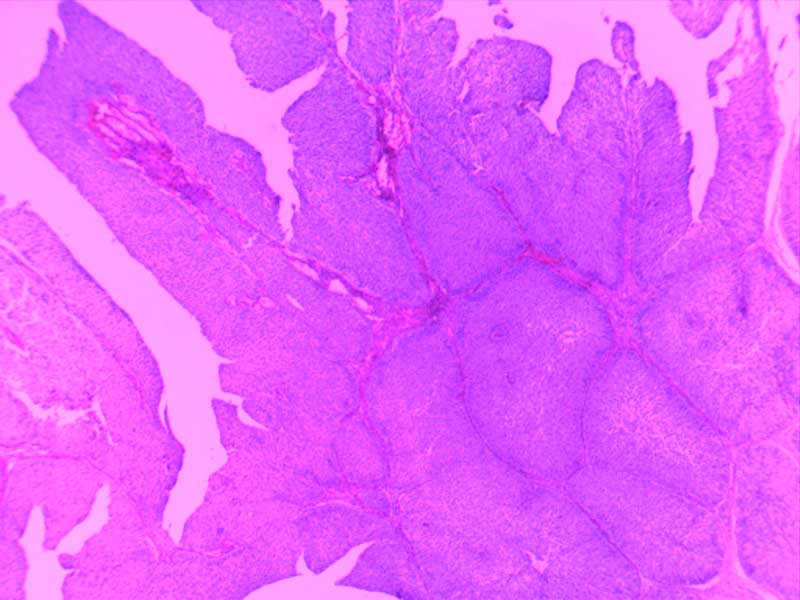

神经鞘瘤4倍

神经鞘瘤-10倍-(2)

神经鞘瘤-10倍

大叶性肺炎(红肝期)10倍